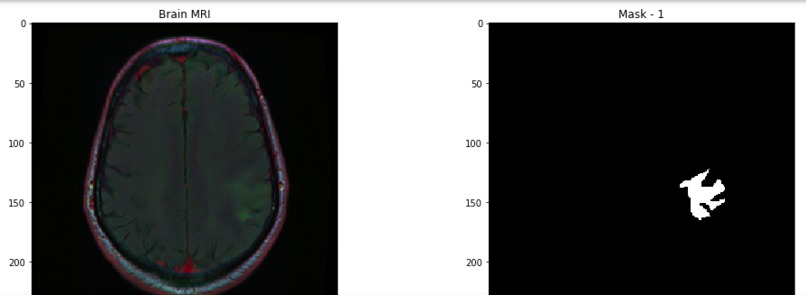

This project will visualize the data (images) first, and display the mask, which will indicate the existence of tumors. Also, ResNet will help this project to improve accuracy.

1. This project will help operators to visualize brain tumors.